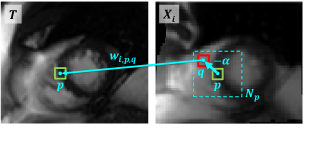

Refer to caption

(a) Non-local patch-based label fusion: each patch, e.g., patch around q𝑞q, in a window Npsubscript𝑁𝑝N_{p} around p𝑝p votes for the label of pixel p𝑝p in T𝑇T.

(b) Shift operation: feature distance between p𝑝p of T𝑇T and q𝑞q of Xisubscript𝑋𝑖X_{i} in (a) equals to feature distance of T𝑇T and Sα(Xi)superscript𝑆𝛼subscript𝑋𝑖S^{\alpha}(X_{i}) at p𝑝p.

Fig. 3: Illustration of non-local patch-based label fusion and shift operation.

Figure 3(a) shows the idea of non-local patch-based label fusion strategy. For simplicity, we use the notation p𝑝p to denote a pixel’s spatial position instead of (m,n)𝑚𝑛(m,n). To account for atlas-to-target image registration errors, all the pixels in a search window around the pixel p𝑝p in warped atlas images {Xi}i=1Ksuperscriptsubscriptsubscript𝑋𝑖𝑖1𝐾\{X_{i}\}_{i=1}^{K} are considered as the potential corresponding pixels for the pixel p𝑝p in target image T𝑇T. Therefore, the labels of these pixels in atlas images are fused to produce the estimated target label at pixel p𝑝p.

To incorporate Eqn.(3) into the neural network as a differentiable function, we decompose the computation of the fusion weights into several successive simple operations, modeled as shift layer, distance layer and weight layer. Each operation and the gradient of its output w.r.t. input can be easily calculated using standard deep-learning libraries. Figure 3 shows our motivation for this decomposition in detail. Instead of directly computing the feature distance of pixel p𝑝p in target image T𝑇T and pixel q𝑞q in atlas image Xisubscript𝑋𝑖X_{i}, shown in Fig. 3(a), we can equivalently compute the per-pixel feature distance at the pixel p𝑝p between target image T𝑇T and the shifted atlas image Xisubscript𝑋𝑖X_{i} by the shift vector α=pq𝛼𝑝𝑞\alpha=p-q, as shown in Fig. 3(b). Suppose that the search window width is 2t+12𝑡12t+1. To calculate the fusion weights using Eqn.(3) in deep networks, we first shift each feature map of Xisubscript𝑋𝑖X_{i} by each shift vector α𝛼\alpha within the non-local region Rnl={(u,v)2|tu,vt}subscript𝑅𝑛𝑙conditional-set𝑢𝑣superscript2formulae-sequence𝑡𝑢𝑣𝑡R_{nl}=\left\{(u,v)\in\mathbb{Z}^{2}|-t\leq u,v\leq t\right\} using a shift layer, then compute the pixel-wise feature distances using a distance layer, and finally transform these distances to fusion weights using a weight layer.